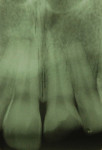

An 18-year-old male patient presented with a visible fracture in the left upper central incisor (tooth No. 9) due to a skateboard accident (Figure 1). The patient did not complain of pain. After the clinical examination, the clinician diagnosed an oblique root-crown fracture of enamel and dentin, with the involvement of the periodontal biologic space but without pulp exposure and mobility (Figure 2). The injury resulted in two dental fragments that were presented by the patient. The fragments were in good condition; they had been properly cleaned and stored in a saline solution for approximately 10 hours, and, in the examination, they adapted to the remaining tooth (Figure 3). The examination, including sensitivity and percussion tests, and the radiographic exams showed normal periapical and periodontal tissues, which gave the appearance of vitality to the damaged tooth, eliminating the need for endodontic treatment (Figure 4 and Figure 5). Thus, since there was no pulp exposure it was proposed to perform only the indirect pulp capping of the pulp-dentin complex, as this was the least invasive approach. The patient was informed about the risks and advantages of the treatment and consented to it.